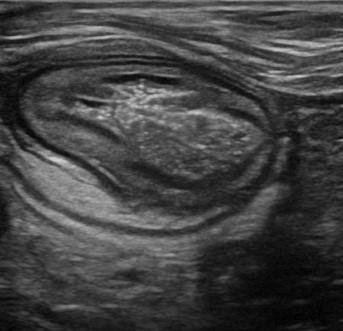

Viêm ruột

» Thông tin: Nữ giới – 55 tuổi.

» Lâm sàng: Tiêu chảy.